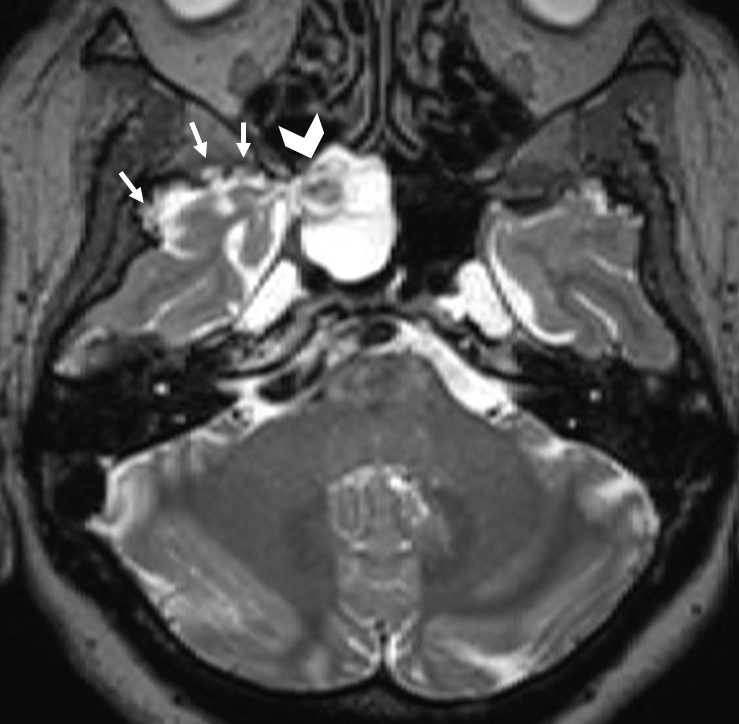

The institutional review board approved this single-center retrospective study. Patients with suspected CSF leakage who underwent MRI with a special protocol between 2012 and 2023 were evaluated. Images of 240 consecutive patients were assessed for CSF leakage by two neuroradiologist with 10 and 3 years of experience. Patients with leakage from sites other than the sphenoid sinus were excluded from the study (n = 220). Six out of 20 patients with a history of trauma or surgery of the sphenoid sinüs or cavernous sinus were also excluded. The remaining 14 patients with sphenoid sinüs CSF leakage formed the study group. Leakage was supported by surgical findings and beta-2 transferrin test. All imaging was performed using 3 Tesla (Verio, Siemens, Erlangen, Germany) or 1.5 Tesla (Aera, Siemens, Erlangen, Germany) MR scanners. The MRI protocol for CSF leakage consisted of T2 weighted fat suppressed coronal plane images with 3 mm slice thickness, T2-weighted sagittal plane SPACE images with 1 mm slice thickness, and CISS coronal plane images with 1 mm slice thickness. All images were evaluated by two radiologist with 4 years of experience in terms of empty sella, enlargement of the Meckel's caves (Figure 1), fluid in the optic nerve sheaths, vertical tortuosity of the optic nerves (Figure 2), arachnoid pits, encephaloceles (Figure 3), and lateral recess pneumatization of the sphenoid sinuses. Lateral recess pneumatization was defined as pneumatization lateral to the line connecting the foramen rotundum and the Vidian canal (Figure 4). The side of the leakage and the other accompanying sites of leakage were noted. The presence of a bony defect was evaluated on CT images (Figure 5).Descriptive statistics were used for data analysis. Continuous variables were presented as mean ± standard deviation [median (minimum?maximum)], and categorical variables were expressed as frequency and percentage.

Figure 2: Sagittal CISS images show fluid in the right (R) and the left (L) optic nerve sheaths (arrowheads) and tortuosity of the optic nerves (arrows). |